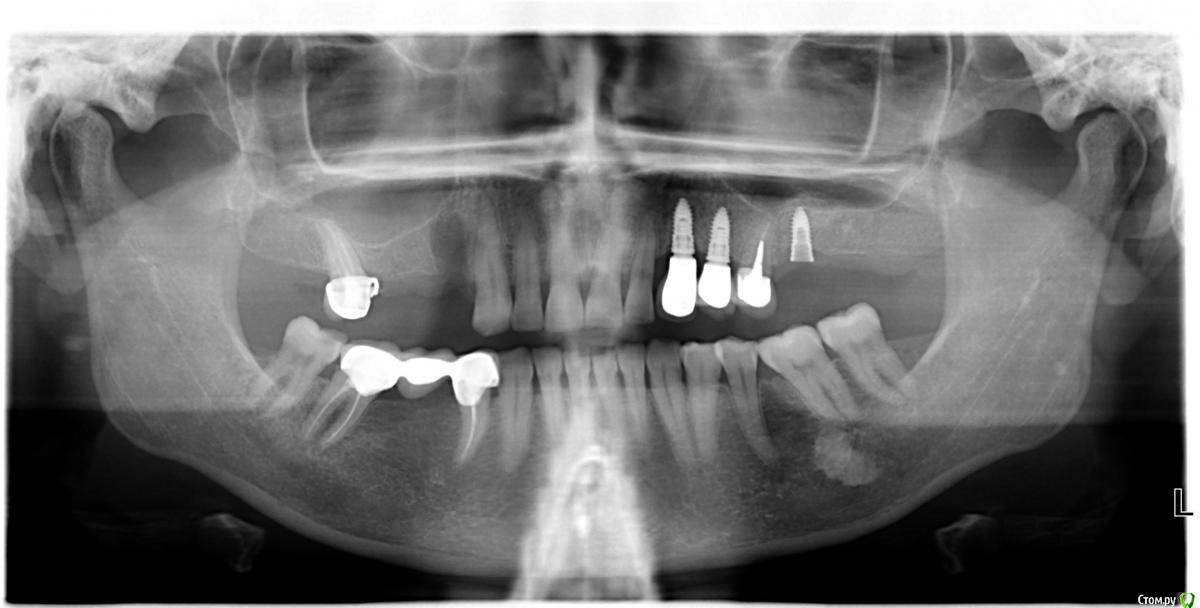

Павел7809 Опубликовано 21 мая, 2018 Поделиться Опубликовано 21 мая, 2018 Приветствую! Собственно ситуация стандартная, коронки кто то поставил, одну из них пациент успешно потерял. Врач укатил в другую страну. Что это за имплант? Ссылка на комментарий

EEcho Опубликовано 21 мая, 2018 Поделиться Опубликовано 21 мая, 2018 Похож на Q-имплант Ссылка на комментарий

Pavel-Pskov Опубликовано 22 мая, 2018 Поделиться Опубликовано 22 мая, 2018 Похож на Q-имплант+ Ссылка на комментарий